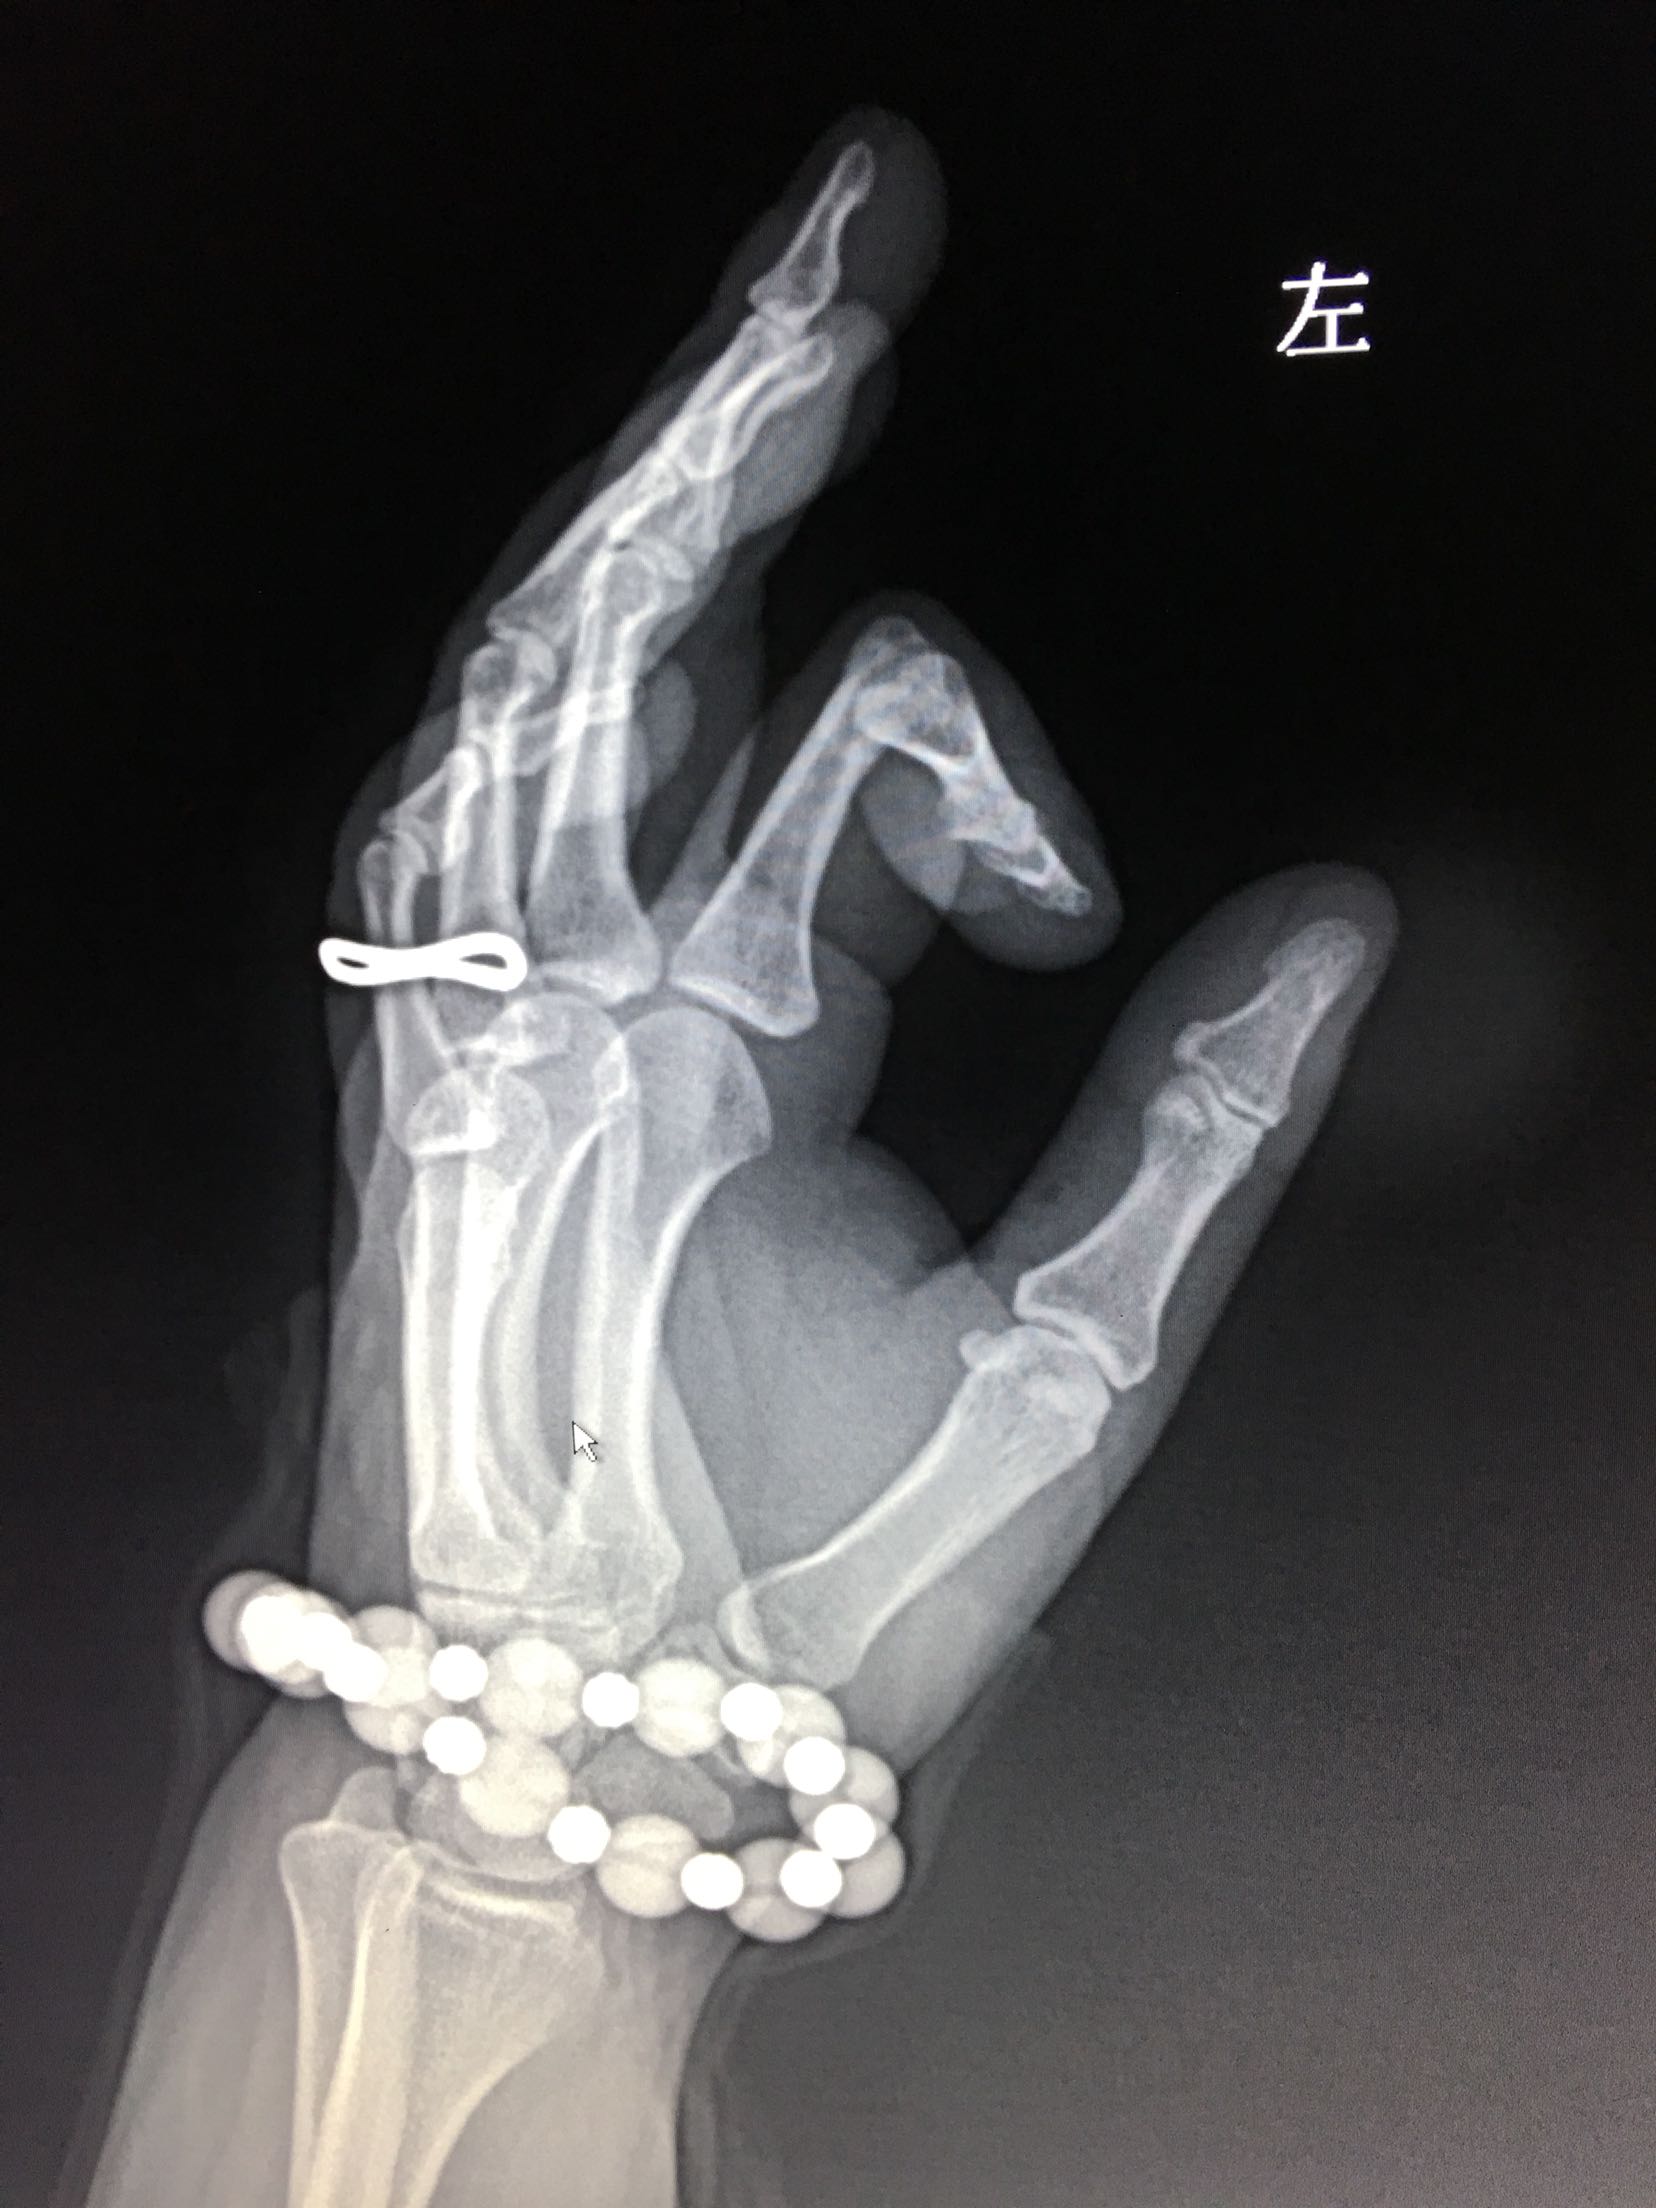

左手食指外伤史现手指畸形